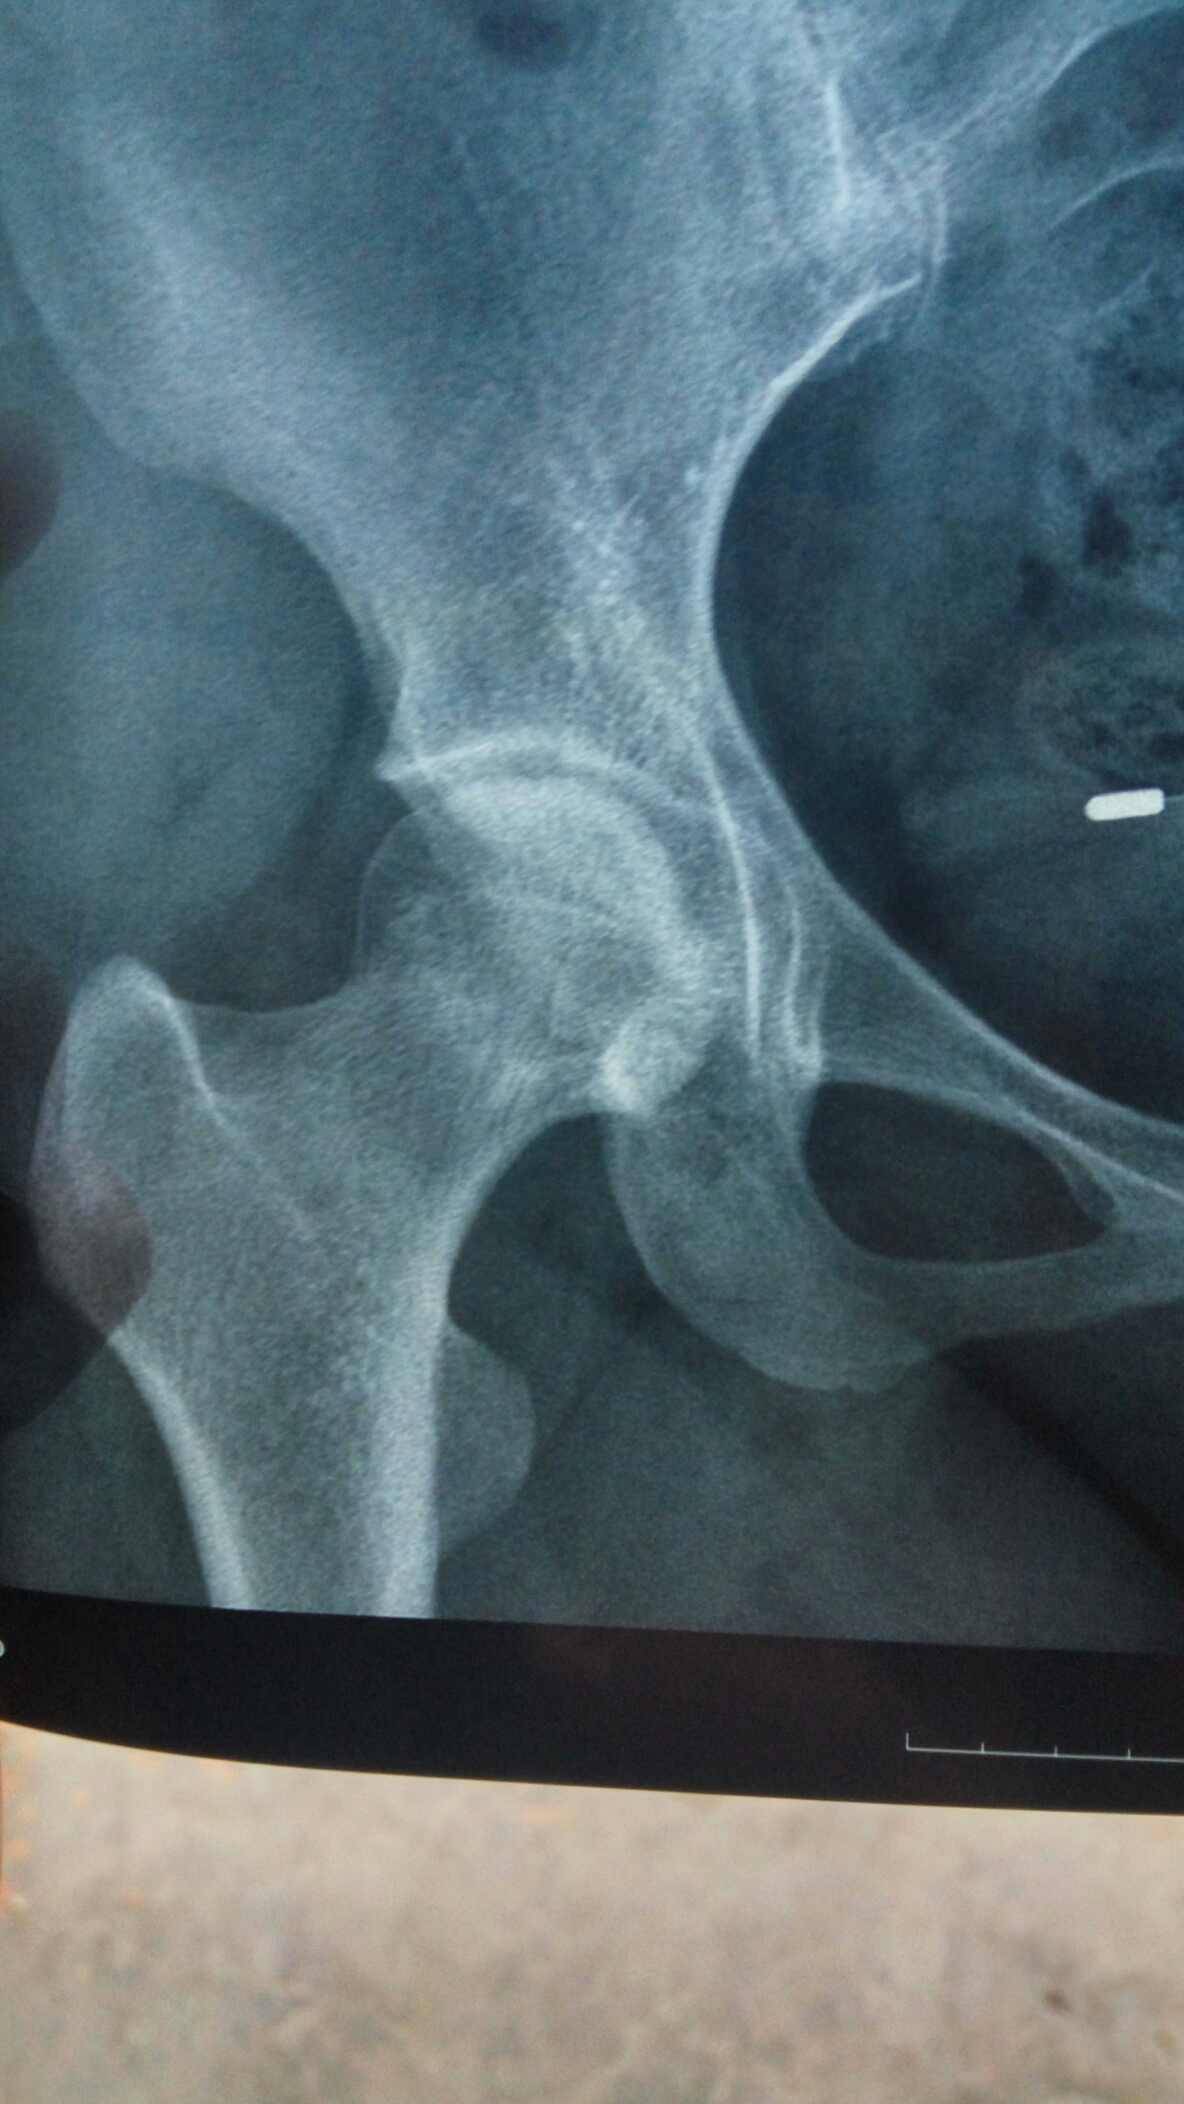

前几天复查一切都还好,就是腿好像比上次严重点,这半年太不注意了走路太多。有会看片子的吗?帮我看看骨质怎么样?前两张是刚拍的,后面一张是去年的。

你右边比较严重啊?有点塌陷了

骨密度看不太出来,股骨头外观形态没太大变化。